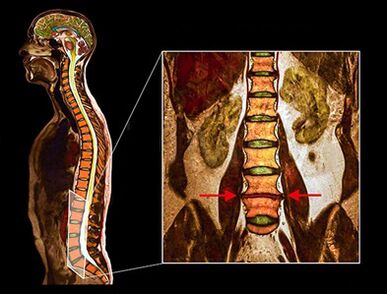

Osteochondrosis (degenerative intervertebral disc disease) in the lumbar spine or in the lower back is caused by involving the intervertebral discs, which lead to pain in the lower back area.

Intervertebral discs are robust, fibrous structures that act as ligaments between the vertebrae, absorb bumps and ensure the shock absorption of the spine.The intervertebral discs are flexible, but strong enough to enable movements such as the forward, reverse or sideways bending of the upper body.

- MRI - This diagnostic method allows you to clarify the degree of degeneration, the presence of fractures, hernias of stenosis discs.Often, an MRI study is required in preparation for surgical treatment to accurately determine the location of the degenerated disc and plan the operation.